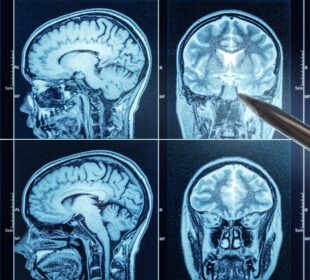

Migrenos sukelti pakitimai smegenų MRT: kaip juos suprasti

Naujausi moksliniai tyrimai rodo, kad migrena neretai pasireiškia tam tikrais smegenų pokyčiais – baltosios medžiagos pažeidimais, kurie matomi atliekant magnetinio rezonanso tyrimą. ...2026 31 kovoAr kalneliai gali sukelti insultą?